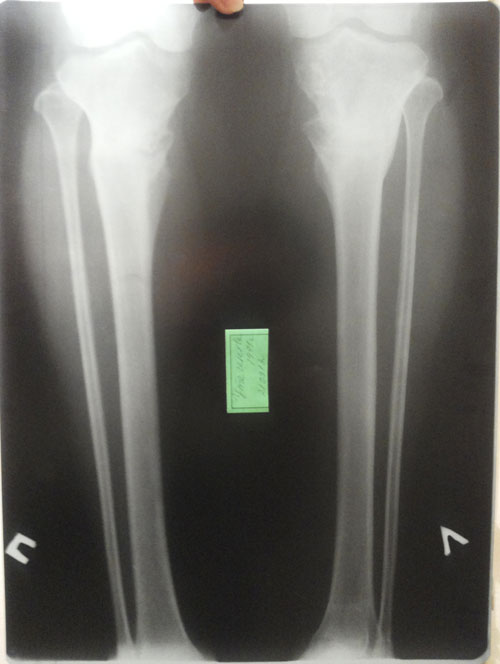

Дата операции 15.01.2013г.

Дата снятия аппаратов 14.06.2013г.

Срок лечения 133 дней.

Переделка после ВОЛГОГРАДА (РОССИЯ)